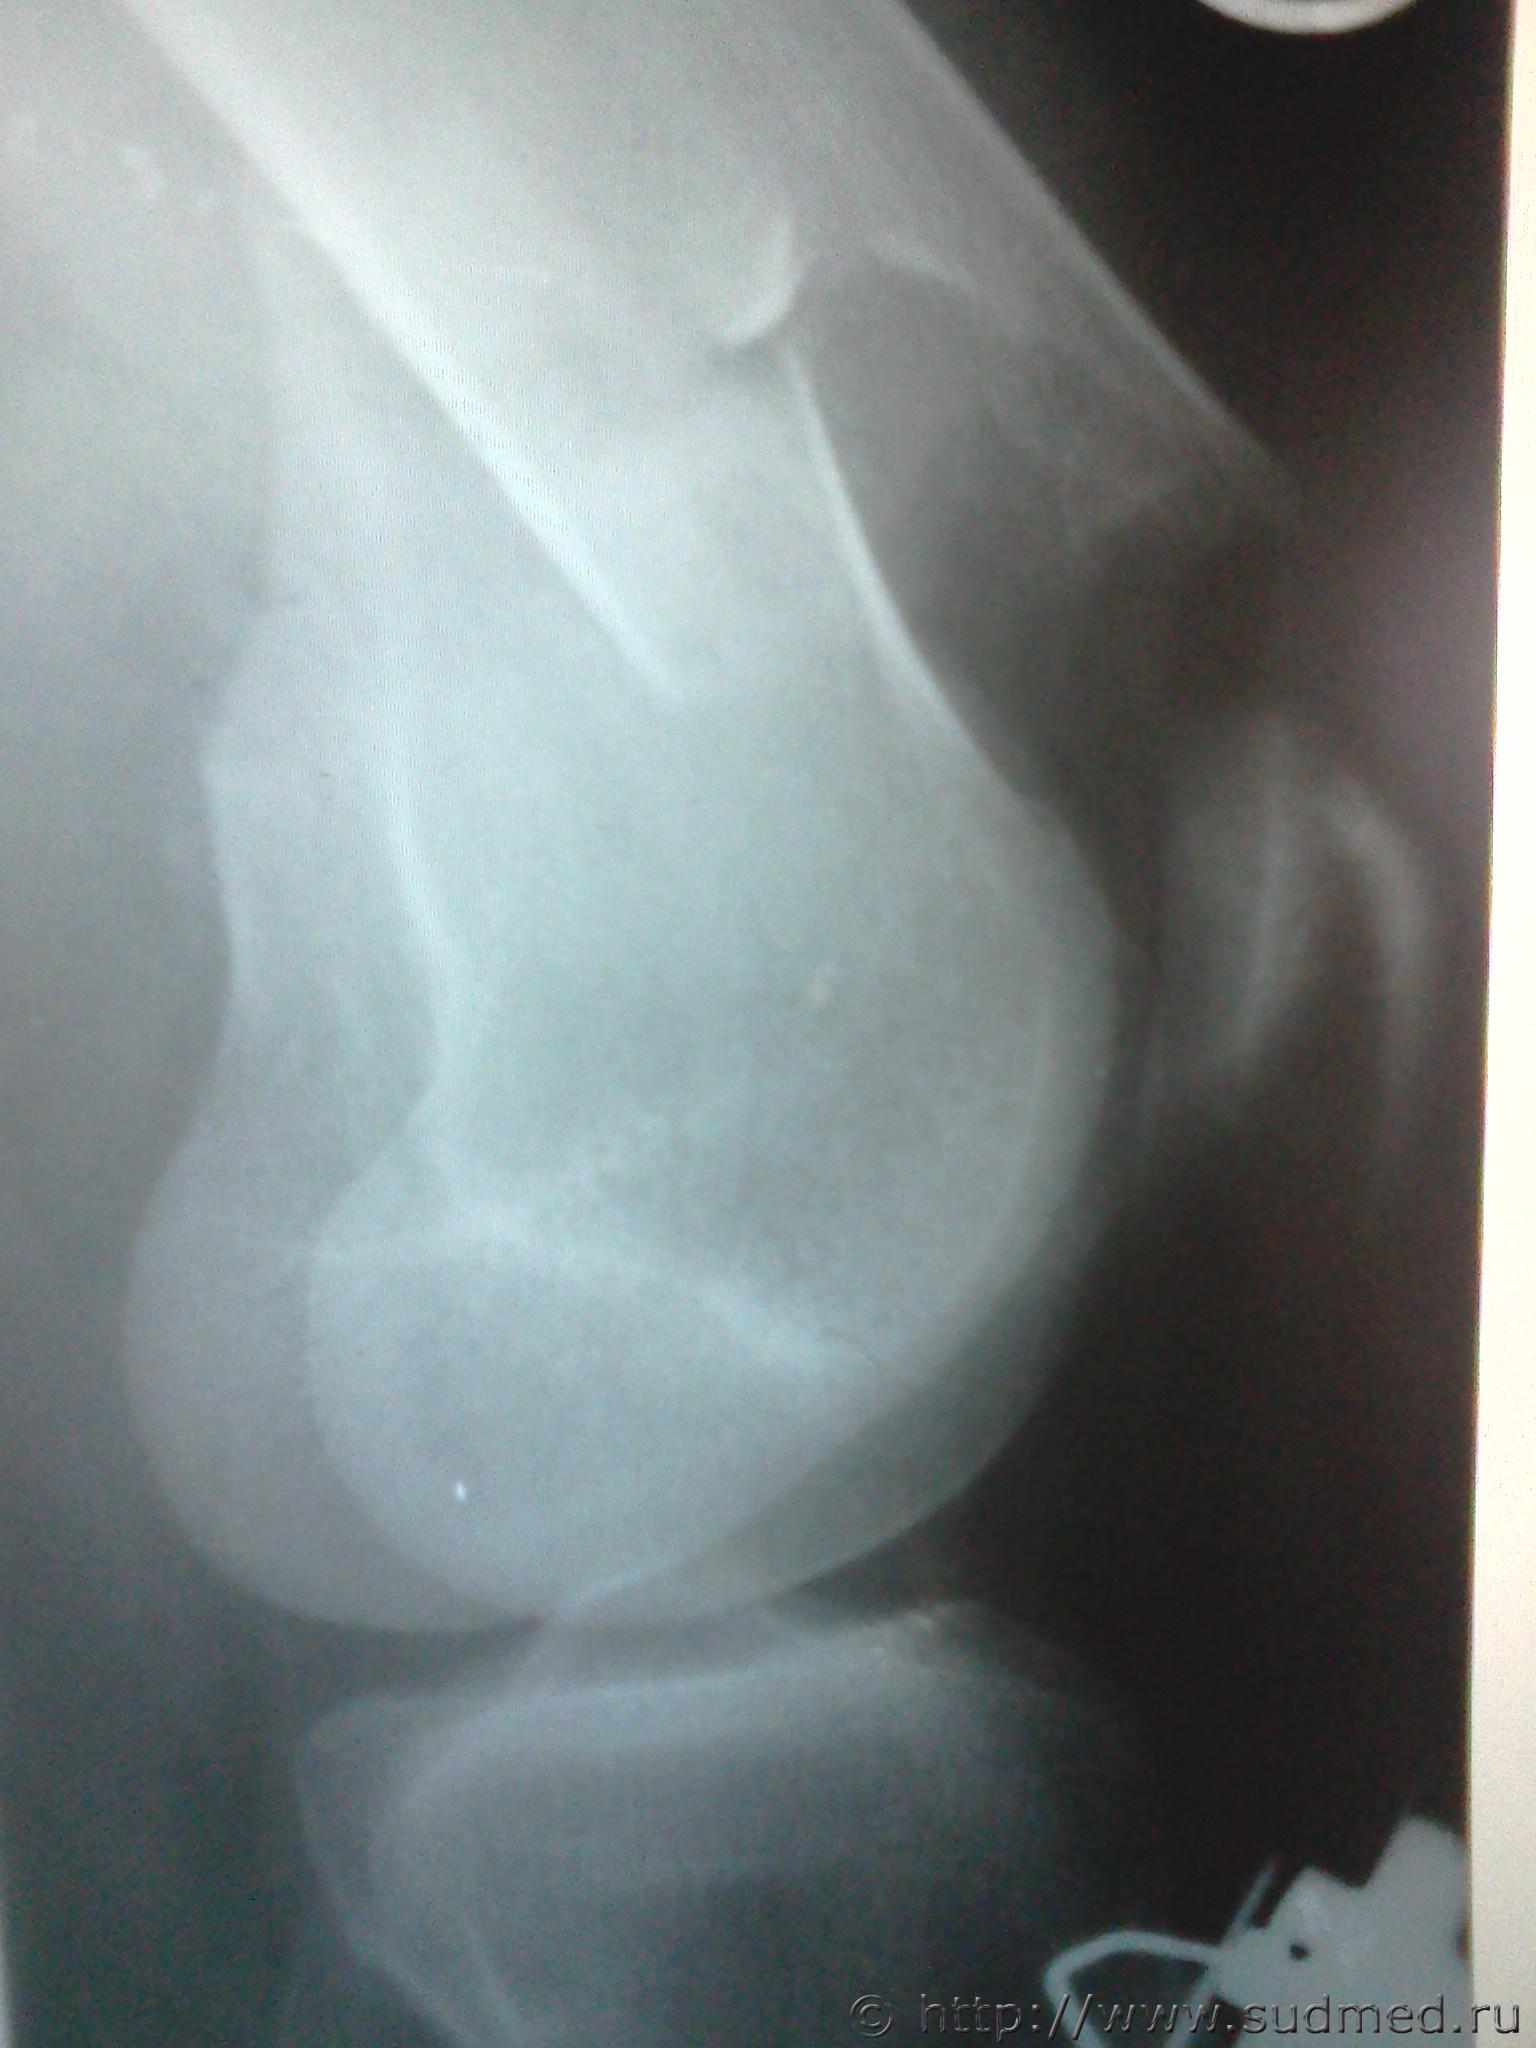

правая бедренная

левая большеберцовая

Эскизы прикрепленных изображений

Судебная медицина - Прикрепленное изображение Судебная медицина - Прикрепленное изображение Судебная медицина - Прикрепленное изображение Судебная медицина - Прикрепленное изображение

Я бы не задумываясь, отнес бы каждый перелом к тяжкому вреду.

Однозначно - тяжкий вред. Перелом диафиза в нижней трети.